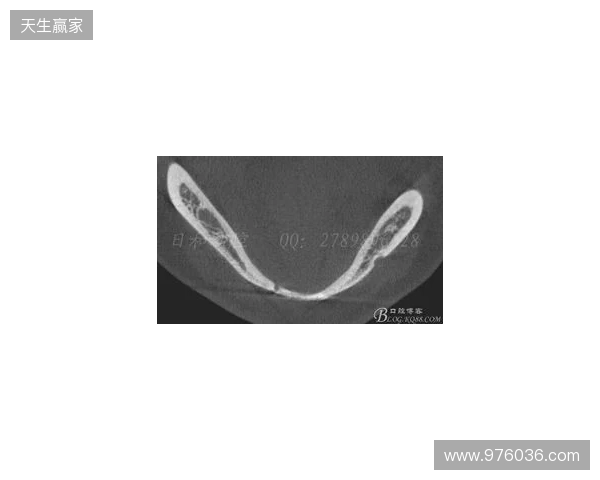

在2026赛季中超联赛首轮的比赛中,韦林顿·席尔瓦遭遇了严重的伤病,导致他上唇部受伤,并且出现了牙齿和牙槽骨的损伤。根据华西口腔医院的诊断,席尔瓦的伤情包括上唇部贯通伤、两颗牙齿半脱位以及上颌前牙区牙槽骨骨折。此事件不仅对球员本人构成了巨大的身体挑战,也给球队带来了不小的影响。伤病的发生让人揪心,球迷们纷纷为席尔瓦送上祝福,希望他能尽快康复,重返赛场。

根据医院的检查结果,韦林顿·席尔瓦的上唇部受伤程度较为严重,属于贯通伤,已经进行了清创缝合。这种类型的伤势不仅影响外观,还可能对球员的饮食和发声造成影响。更为严重的是,他的上颌前牙区还出现了骨折,意味着席尔瓦在恢复期间将面临长时间的治疗和康复过程。

球员的第11和第21牙出现了半脱位的情况,这可能会导致他在恢复后需要进行进一步的牙科治疗,甚至有可能影响到他今后的职业生涯。医生表示,虽然通过手术和治疗可以恢复,但心理层面的恢复同样重要。